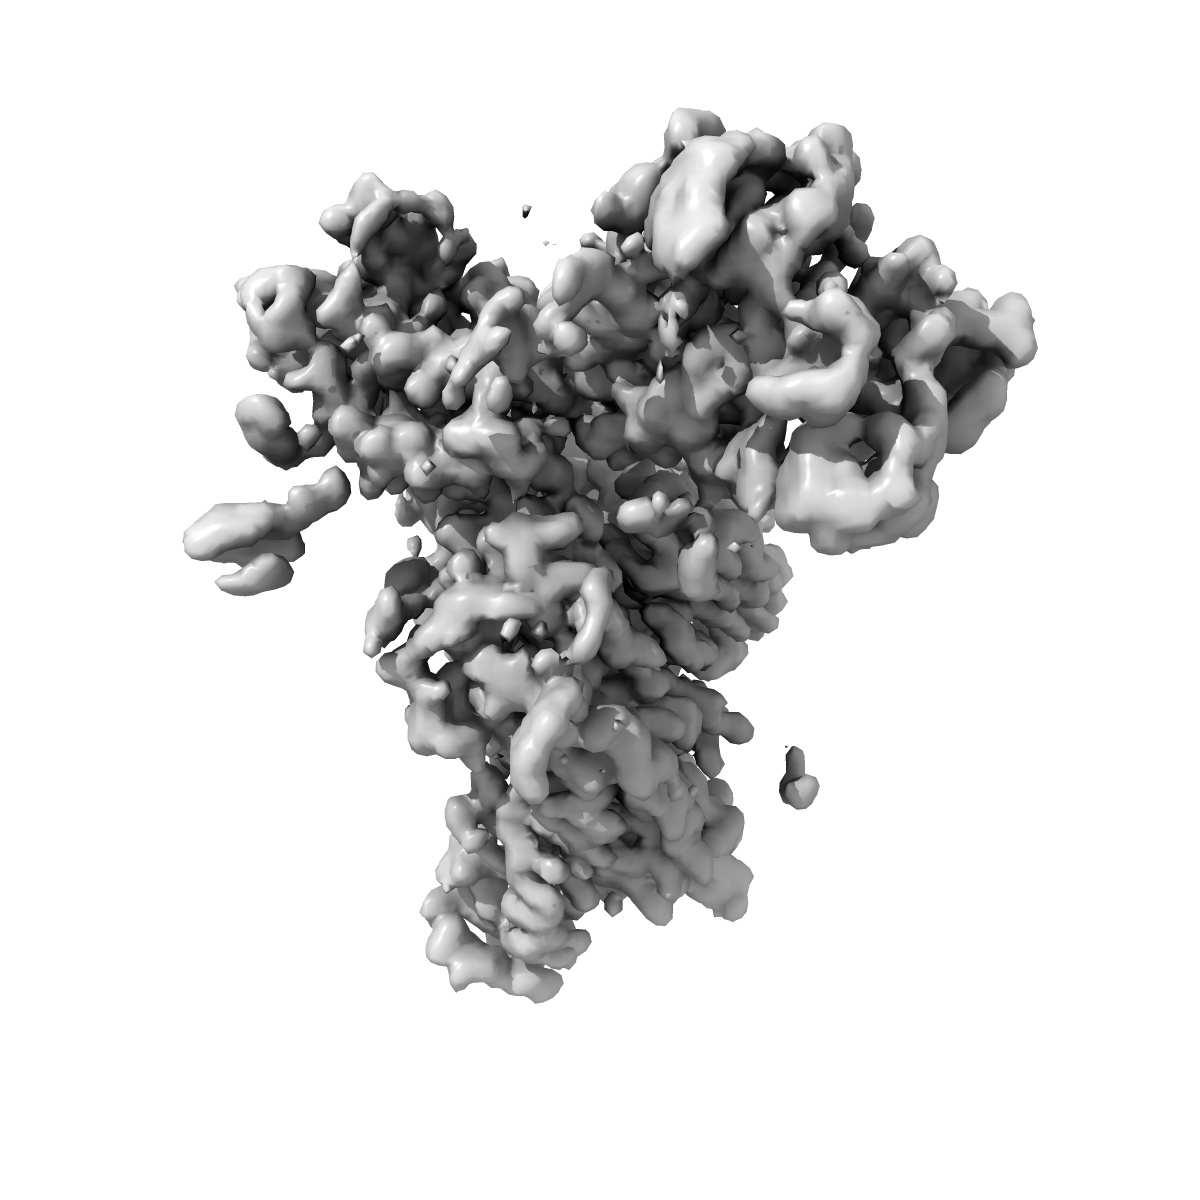

EMD-37161

Monomer state of SARS-CoV Spike protein complexed with antibody PW5-535

Single-particle3.54 Å

Sample: SARS spike protein (S) in complex with broadly neutralizing antibody PW5-535

Fitted models: 8kek